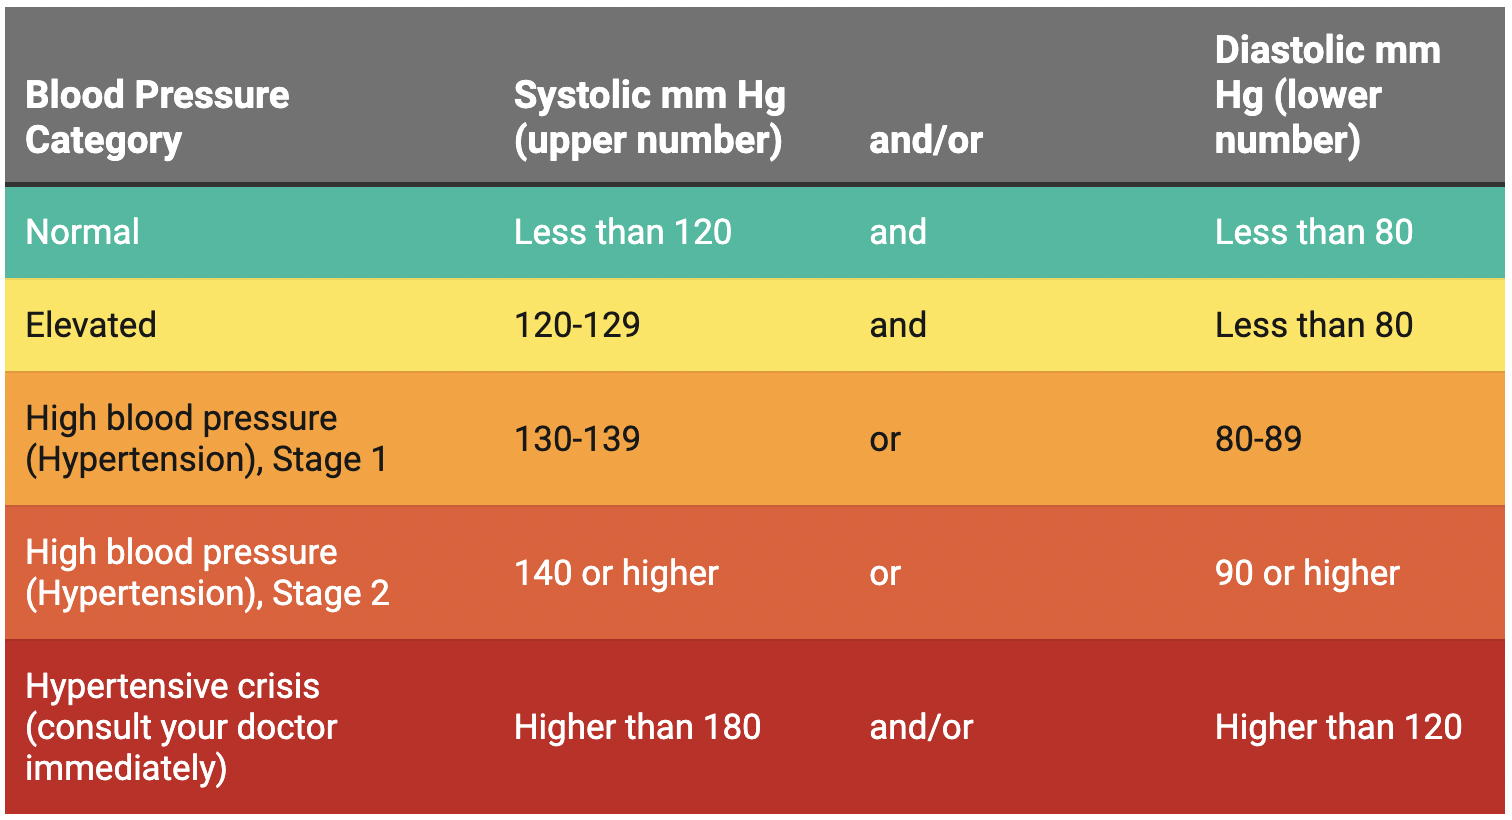

High Blood Pressure Hypertension Texas Heart Institute

Hypertension Types Stages Causes Symptoms Treatments